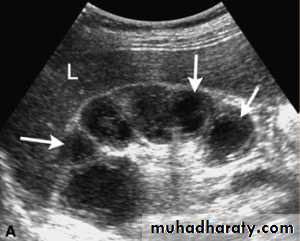

Polycystic renal disease in ultrasound demonstrate numerous cysts seen in cortex & medulla